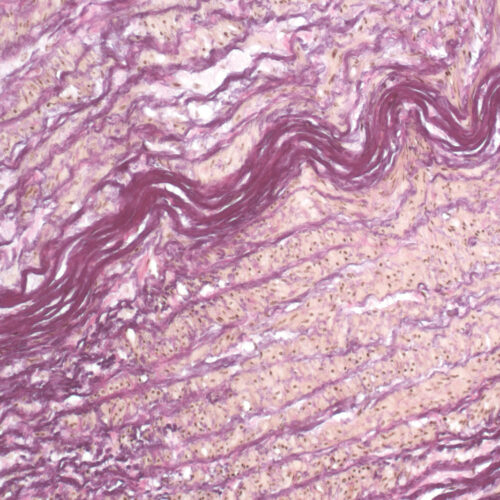

Weigert-Van Gieson kit

Six-reagent kit for staining elastic fibers with a prolonged incubation period. Used for differentiation between elastic tissue, collagen and other types of connective tissue.